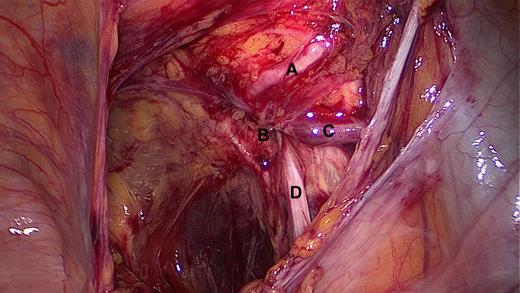

We performed an emergency laparoscopic transabdominal preperitoneal plasty (TAPP) to repair the hernia. During laparoscopy no herniated small bowel was present, but an erythema of a small bowel loop was seen not justifying a resection. The peritoneum forming the hernia sac was mobilized and opened. The hernia orifice could be displayed as shown in Fig. 2.

Intra-operative view after opening the peritoneum, showing the corona mortis (A) just above the obturator hernia orifice (B), the obturator vein with underneath the obturator artery (C) and the obturator nerve (D).

Apart from the obturator nerve and vessels, we detected a vessel crossing the pubic bone: the corona mortis (Fig. 2A). This vessel was spared from extra manipulation and the hernia closed with a monocryl-prolene mesh that was fixed with titanium tacks.